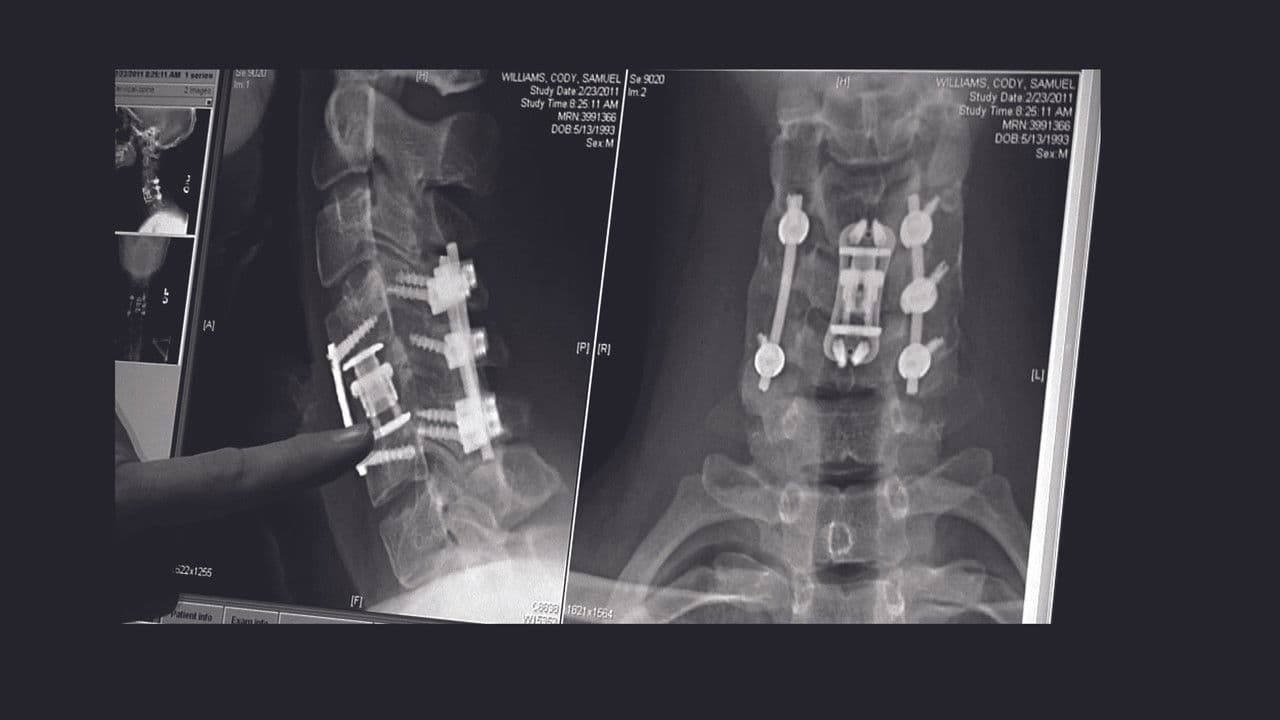

Cody Williams